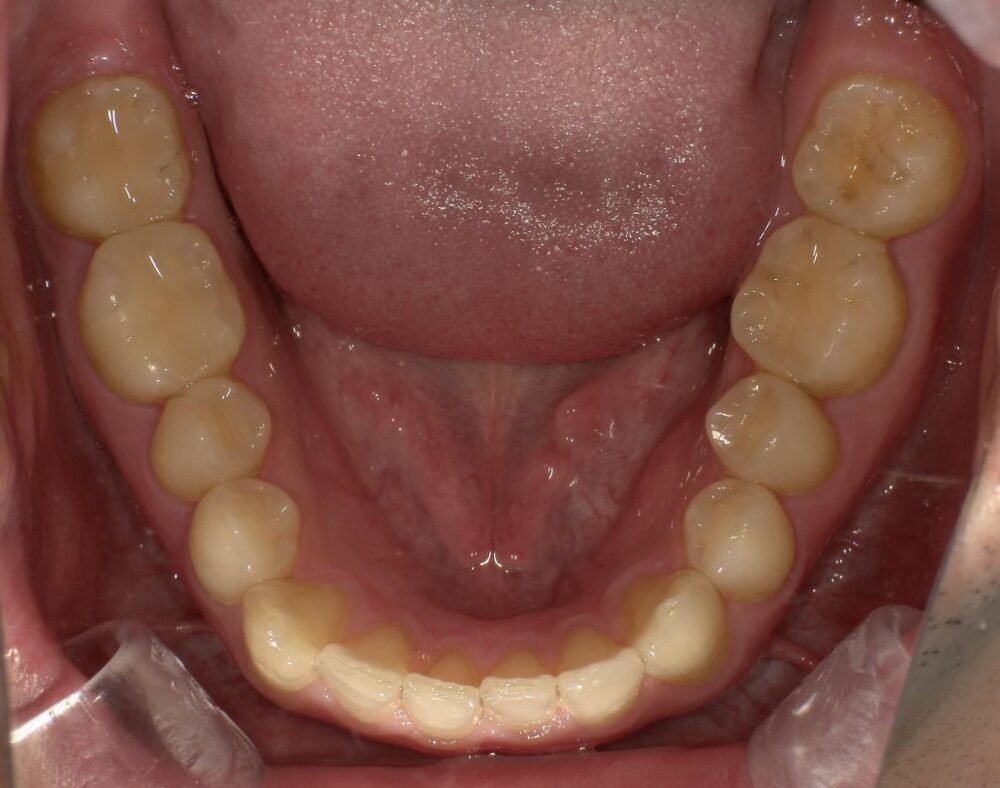

症例3

治療後

| 主訴 | 虫歯を治したい |

|---|---|

| 診断 |

2次虫歯 |

| 治療内容 | 保険CAD インレーによる修復治療 |

| 年齢・性別 |

29歳男性 |

| 治療期間 |

2ヶ月 |

| 治療費用 | 保険に準ずる。 |

| リスク・副作用 | CADの破折、着色 |